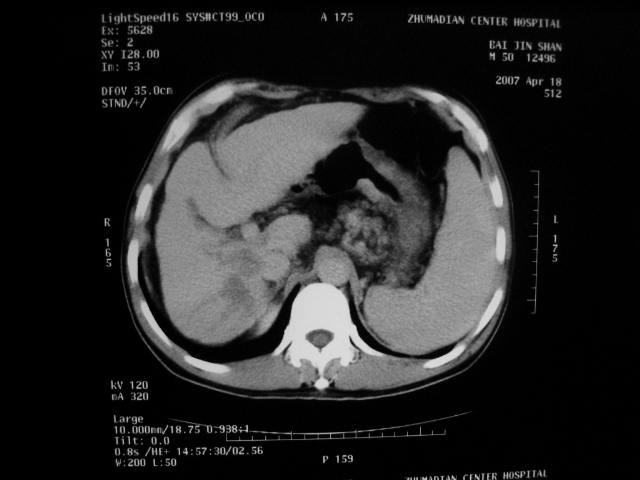

标题: CT7751:病人,50岁,肝硬化多年,行CT三期扫描 [打印本页]

标题: CT7751:病人,50岁,肝硬化多年,行CT三期扫描

动脉期病灶见轻度强化,考虑肝癌可能性大。

动脉期轻度强化 考虑 肝右叶小肝癌可能性大

肝硬化 脾大 胃底静脉曲张 肝癌 门腔间淋巴结肿大

1、肝右叶低密度灶考虑肝癌

2、肝硬化

肝硬化、脾大,静脉曲张,肝右叶低密度灶,增强无明显强化,还是考虑肝癌可能性大,建议结合afp检查。

考虑肝硬化,脾大,静脉曲张,肝右叶低密度灶,右肝癌可能性大。

肝癌分为肝细胞性和胆管细胞性,从强化表现来看,确切地说应是胆管细胞癌.